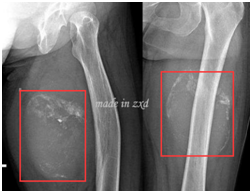

滑膜肉瘤患者与医学影像(图上)